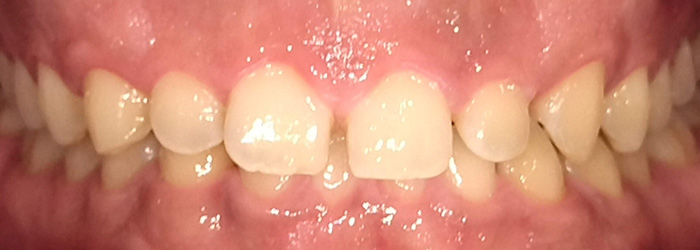

Before

After

インビザラインによる全体矯正後に補綴治療を行い、咬合と審美性を総合的に改善した症例です。

まずマウスピース型矯正装置(インビザライン)により歯列および咬合関係を整え、その後、必要部位にジルコニア補綴を行いました。

矯正のみ・補綴のみではなく、両治療を組み合わせることで機能性と審美性の両立を目指した包括的治療です。

奥歯の噛み合わせと前歯の歯並びを同時に改善した症例(インビザライン+ジルコニア)

【治療前の状態】

患者様は、奥歯でしっかり噛めないことと、前歯の歯並びの乱れを気にされ来院されました。診査の結果、前歯部の叢生(歯並びの乱れ)と、臼歯部の離開咬合(奥歯がしっかり噛み合っていない状態)が認められました。また、臼歯部には古い金属修復物が装着されており、機能面だけでなく審美面においても改善が必要な状態でした。

【治療後】

前歯の歯並びが整い、見た目の改善が認められました。また、奥歯でしっかり噛める状態となり、咬合機能の回復が得られています。

【治療のポイント】

本症例では、歯並びの改善だけでなく、噛み合わせの回復と審美性の向上を同時に行っています。当院は一般歯科と矯正治療の両方に対応しているため、矯正治療後に別の医療機関で補綴治療を行う必要がなく、一貫した治療計画のもとで治療を完結することが可能です。また、奥歯の噛み合わせを矯正治療のみで改善する場合、治療期間が長くなることがありますが、本症例では補綴治療(アンレー)を併用することで、比較的短期間で咬合の改善を行いました。さらに、古い金属修復物をジルコニアに置き換えることで、見た目の改善と機能性の両立を図っています。